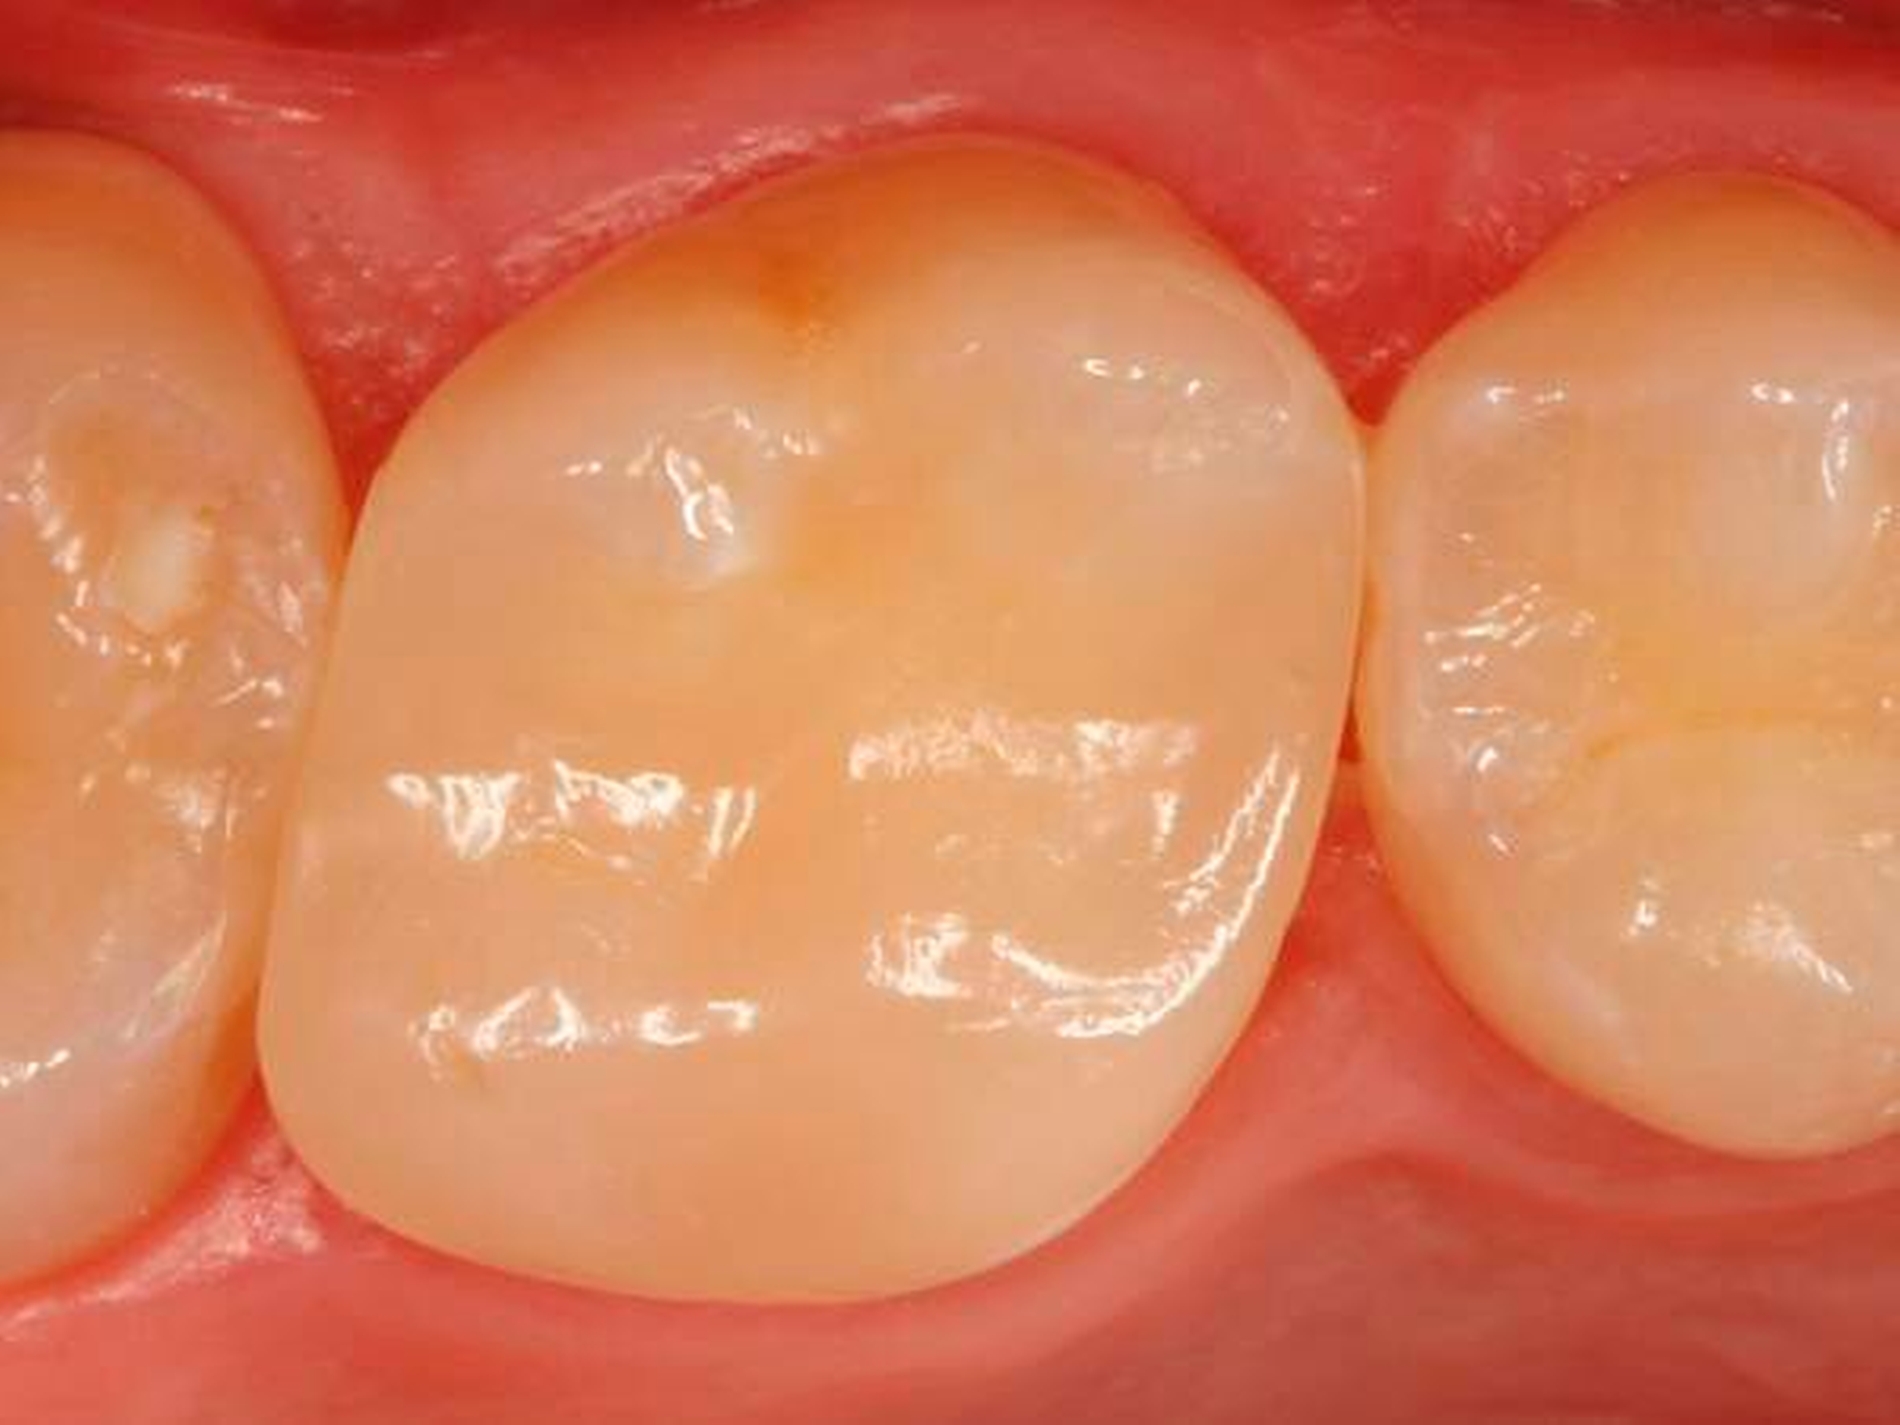

Abbildung 4 zeigt die fertig ausgearbeitete und polierte Restauration unmittelbar nach Behandlungsabschluss, Abbildung 5 bei einer weiteren Kontrolle nach einem Jahr: Der Zahn war inzwischen komplett beschwerdefrei, zeigte im Sensibilitätstest vergleichbare Reaktionen wie die Nachbarzähne. Die Oberfläche erschien allerdings etwas matt, was aber durch eine kurze Nachpolitur (Sof-Lex Polierrad „sehr fein“, 3M) wieder in eine hochglänzende Oberfläche verwandelt werden konnte (Abb. 6). Die Restauration integrierte sich ästhetisch und funktionell optimal in die umgebende Zahnhartsubstanz.

Abbildung 7 zeigt die in der Recall-Sitzung angefertigte Routine-Bissflügelaufnahme, aus der die geringe vertikale Dimensionierung der Versorgung gut erkennbar ist. Die Patientin war mit dieser Neuversorgungsvariante hochzufrieden. Eine Neuversorgung mit einer indirekten Restauration erscheint somit zunächst nicht erforderlich. Auf diese Weise konnte der Zahn mit (im Vergleich zu den angedachten indirekten Restaurationsvarianten) vergleichbar geringem Aufwand zahnhartsubstanzschonend neu versorgt werden.